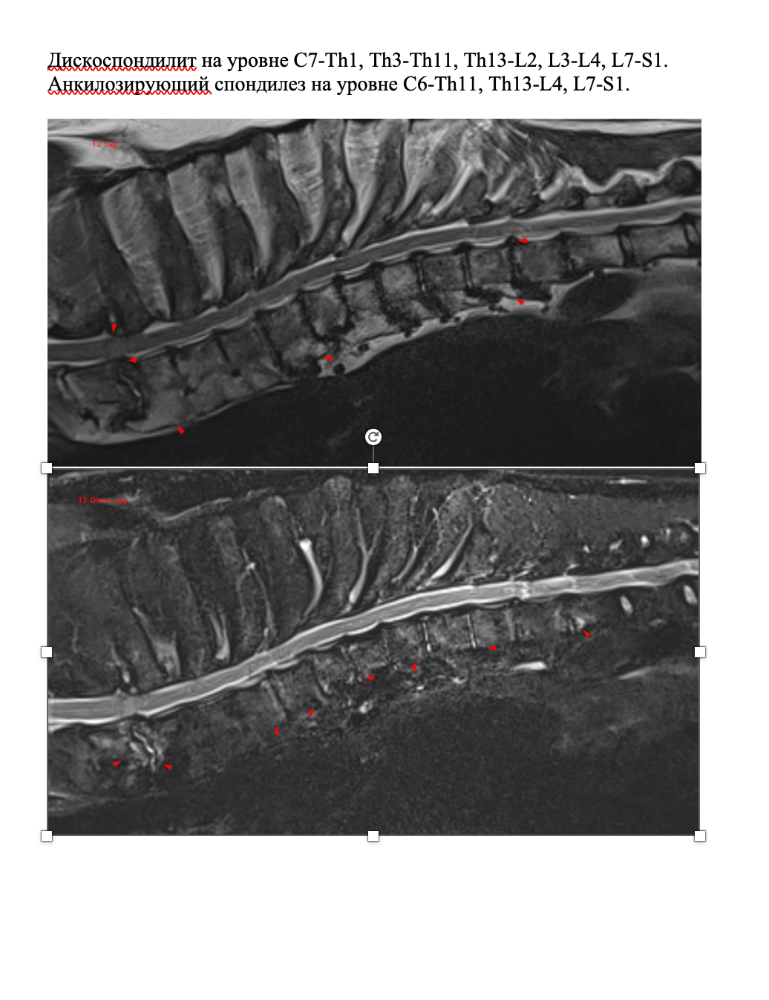

Mosfilmka & Remy Опубликовано 12 мая, 2022 Опубликовано 12 мая, 2022 (изменено) К сожалению, хороших новостей у нас нет... Мы сделали МРТ, результат ниже. Простынь перечисленных проблем... С этим мы пошли к Курганской, уже без Гуру, потому что мотать его туда-сюда снова и трясти в машине ну совсем уже не хотелось. Итог - уколы нам делать нельзя, позвоночный столб воспален, несмотря на долгую антибиотикотерапию. Делать операцию на проблему зада - вся нагрузка упадет на перед, боимся, он просто этого не выдержит. И после этой операции последует операция на перед как заживет зад... Сменили антибиотик по назначению доктора. В общем, все очень печально, ребенок не может сам ходить, лапы отказывают... Дела делает с поддержкой. ?Арине и Сергею низкий поклон за заботу о старичке!! Вспоминаю Старочку и понимаю - как это - ухаживать за собакой, которая постепенно обездвиживается... Баланс 35 141₽ Пополнения: 200руб Лада-Ладушка 3100руб ВИКТОРИЯ 2000руб Печатный экспресс 1300руб пенсия апрель 10000руб пенсия май Итого пополнения: 16600руб Расходы: 528руб аптека 10000руб зоотакси туда-обратно 18500руб МРТ 3500руб прием Курганской Итого расходы: 32528руб ИТОГО БАЛАНС: 19 213₽ Изменено 12 мая, 2022 пользователем Mosfilmka & Remy 3